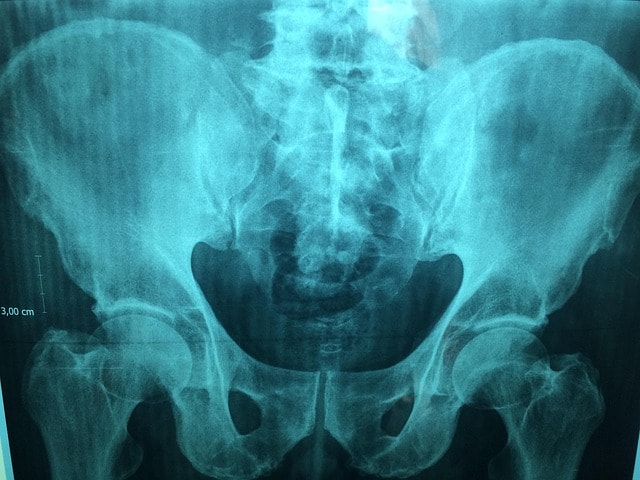

För att utesluta andra orsaker till smärtan kan det bli aktuellt med bilddiagnostik, såsom ultraljud, röntgen eller magnetkamera (MR). Dessa undersökningar hjälper till att upptäcka förändringar i bäckenet, lederna eller andra strukturer som kan ge upphov till besvären. Hos kvinnor kan även gynekologiska undersökningar vara nödvändiga för att utreda smärta i nedre delen av magen och bäckenet. En korrekt diagnos är grunden för att kunna ge rätt behandling och minska smärtan på ett effektivt sätt.